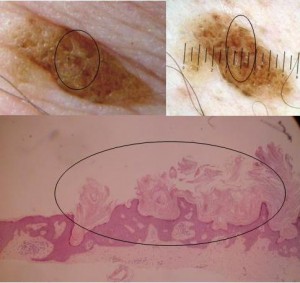

C. Hyperkeratotic (AHCS) {Pierson, 2003}

Also called papillomatous, or digitate, or serrated SK, this type is histologically opposed to the acanthotic type.

In the epidermis, hyperkeratotic SKs can display acanthosis, but are characterised by an important papillomatosis and hyperkeratosis. The epidermal keratinocyte projections towards the stratum corneum have a church-spire appearance.

Squamous like cells are more numerous than basaloid cells. Abundant pigmentation is typically absent. Pseudocysts rarely keratinize.

Acanthohyperkeratotic type of SK: the sharp projections adjoining the stratum corneum are called church spires

Ruguous surface are more evolutive SK with a histological diagnosis of Acanthohyperkeratotic type (AHCS). This corresponds to a thick stratum corneum.

Smooth appearing young SK with a histological diagnosis in the Reticulo-acanthosic type (RA). This corresponds to a thin stratum corneum.

Clinically smooth lesions were of the reticulate and/or acanthotic type and keratotic lesions were of the acanthohyperkeratotic type. If we consider that SK have pulsed stimulations to hyperproliferate or to accumulate, we can admit that all SKs evolve from paucicellular smooth lesions of the reticulate-acanthotic type to pluricellular thickened SK of the acantho-hyperkeratotic type. These paucicellular smooth lesions arise from macular SK, considered by some a solar lentigo. No clonal SKs were detected in our study and their probable rarity does not enable us to hypothesize a relationship between the clinical and histological picture of this subtype.